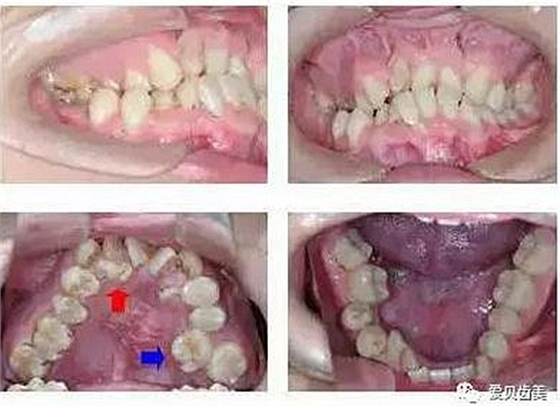

以下圖:是不是大家平時的常見問題。

這就是由于蛀牙引起的臉腫,多見于3-6歲的幼兒。因為蛀牙沒有及時治療,牙根發(fā)炎,向?qū)殞毷杷傻拿娌拷M織擴(kuò)散,引起臉腫。腫的位置與蛀牙的位置相對應(yīng),如果是上門牙引起的一般是上嘴唇腫,后面牙齒引起的就是臉頰腫,上面牙齒引起的臉腫較嚴(yán)重的還會引起下眼瞼腫。